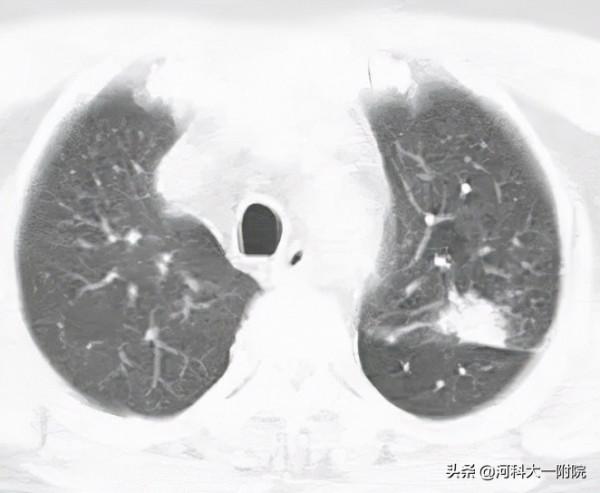

經頭顱MRI、腰穿檢查後,醫生在陳先生腦脊液細胞內發現多個腫瘤細胞,確診其為腦膜癌。由於肺癌是引起腦膜癌病最主要的惡性腫瘤,隨後,醫生又為陳先生完善了胸部CT檢查、肺穿刺活檢,確診其為肺腺癌轉移腦膜癌。